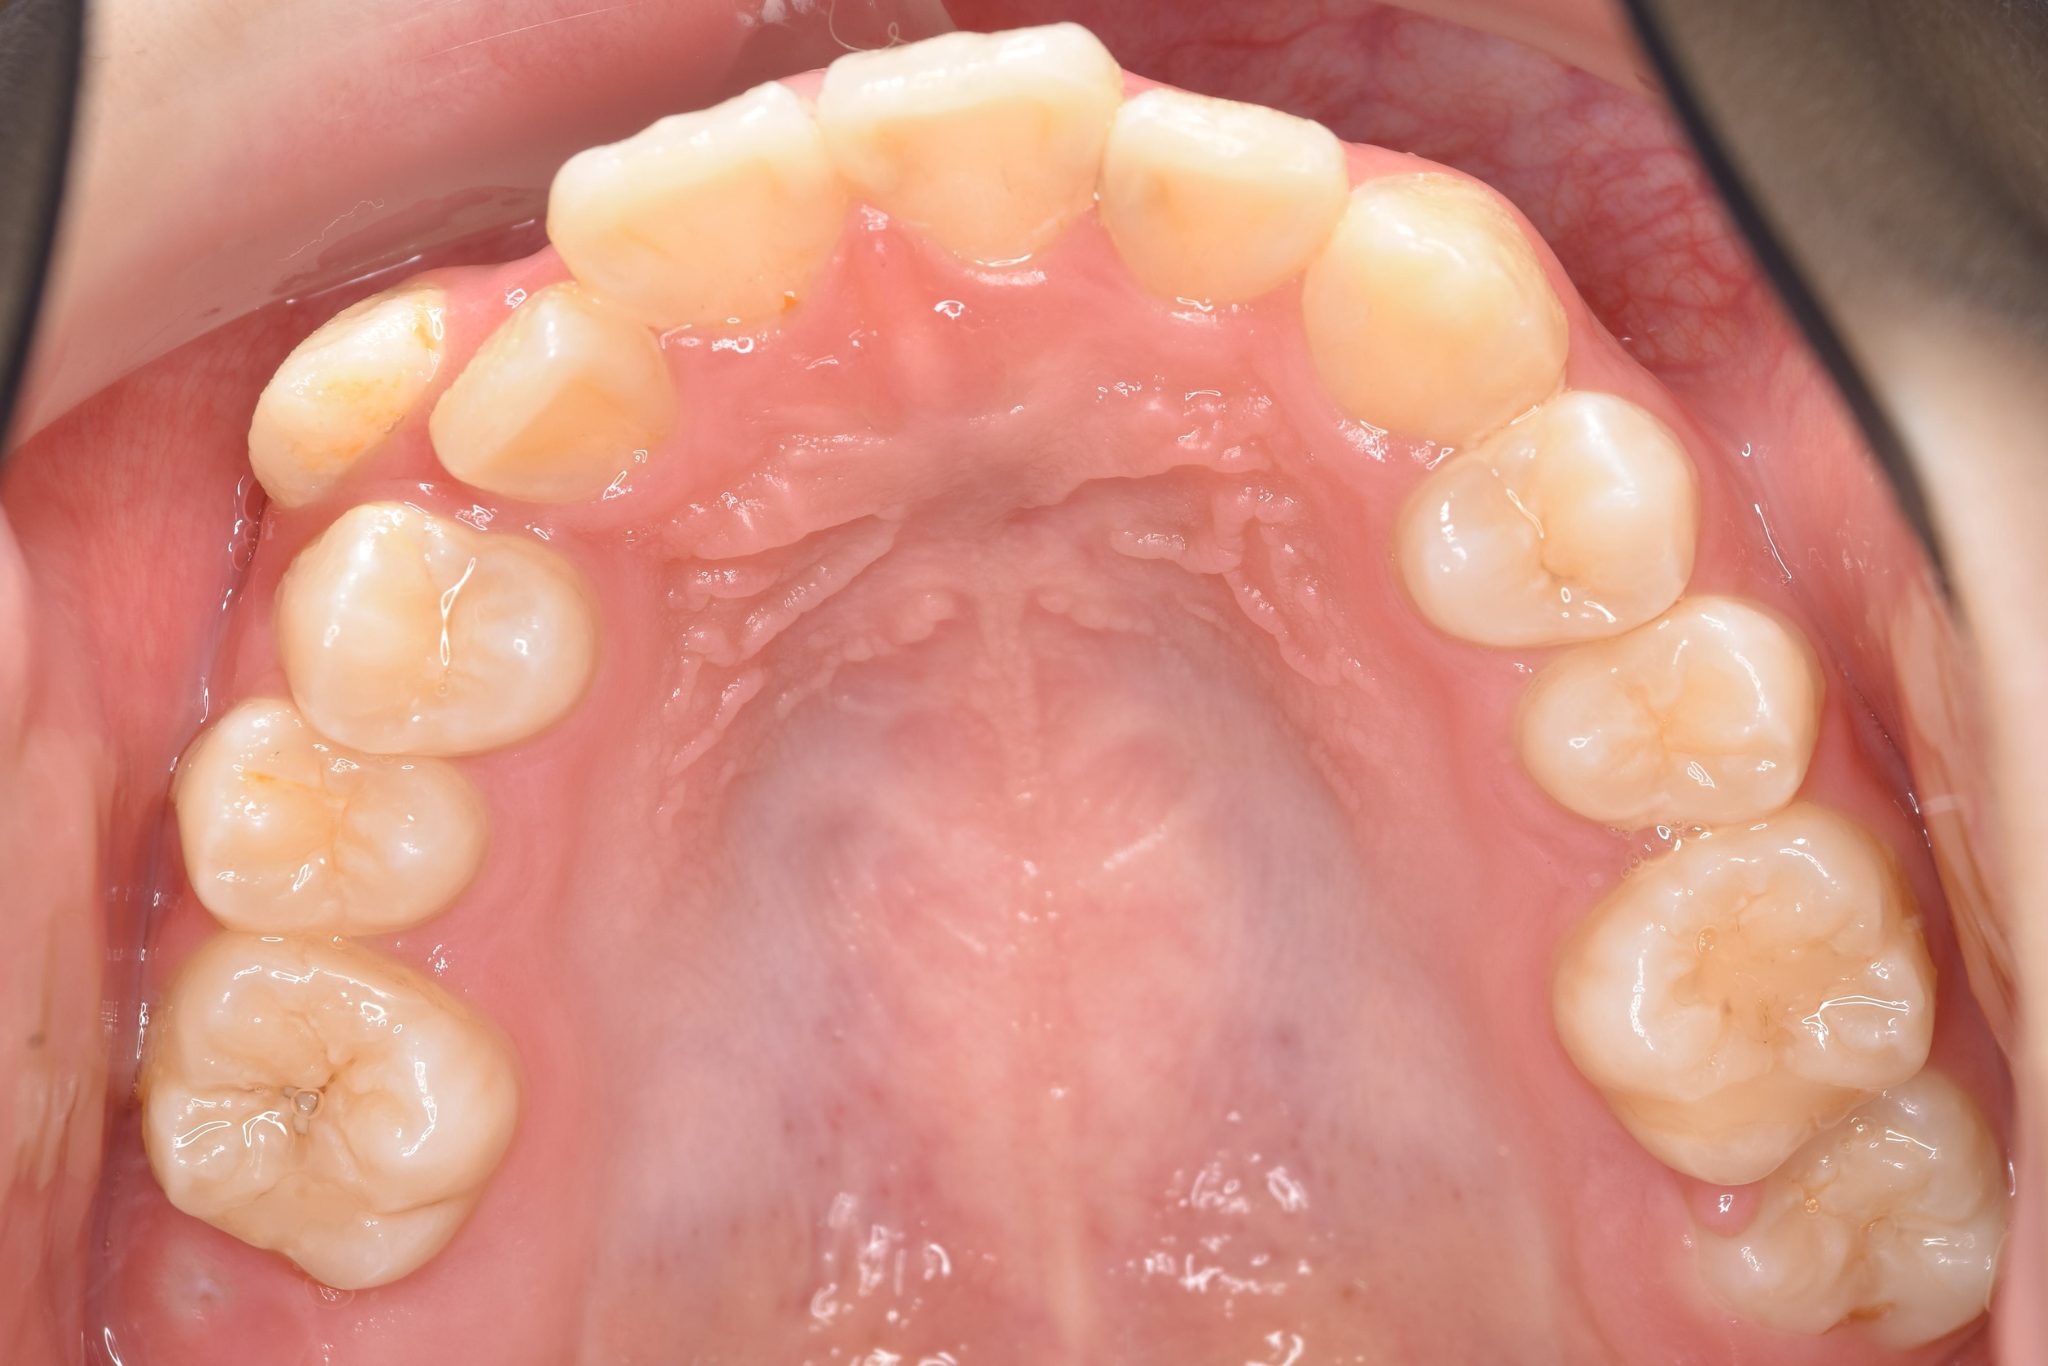

全顎ワイヤー矯正 症例_805